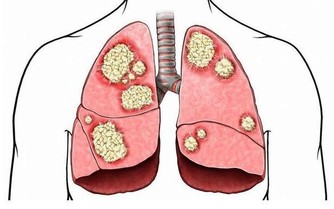

在新型肺炎的高危時期,禽流感又​​捲土重來了,讓大家的惶恐又加重了許多!